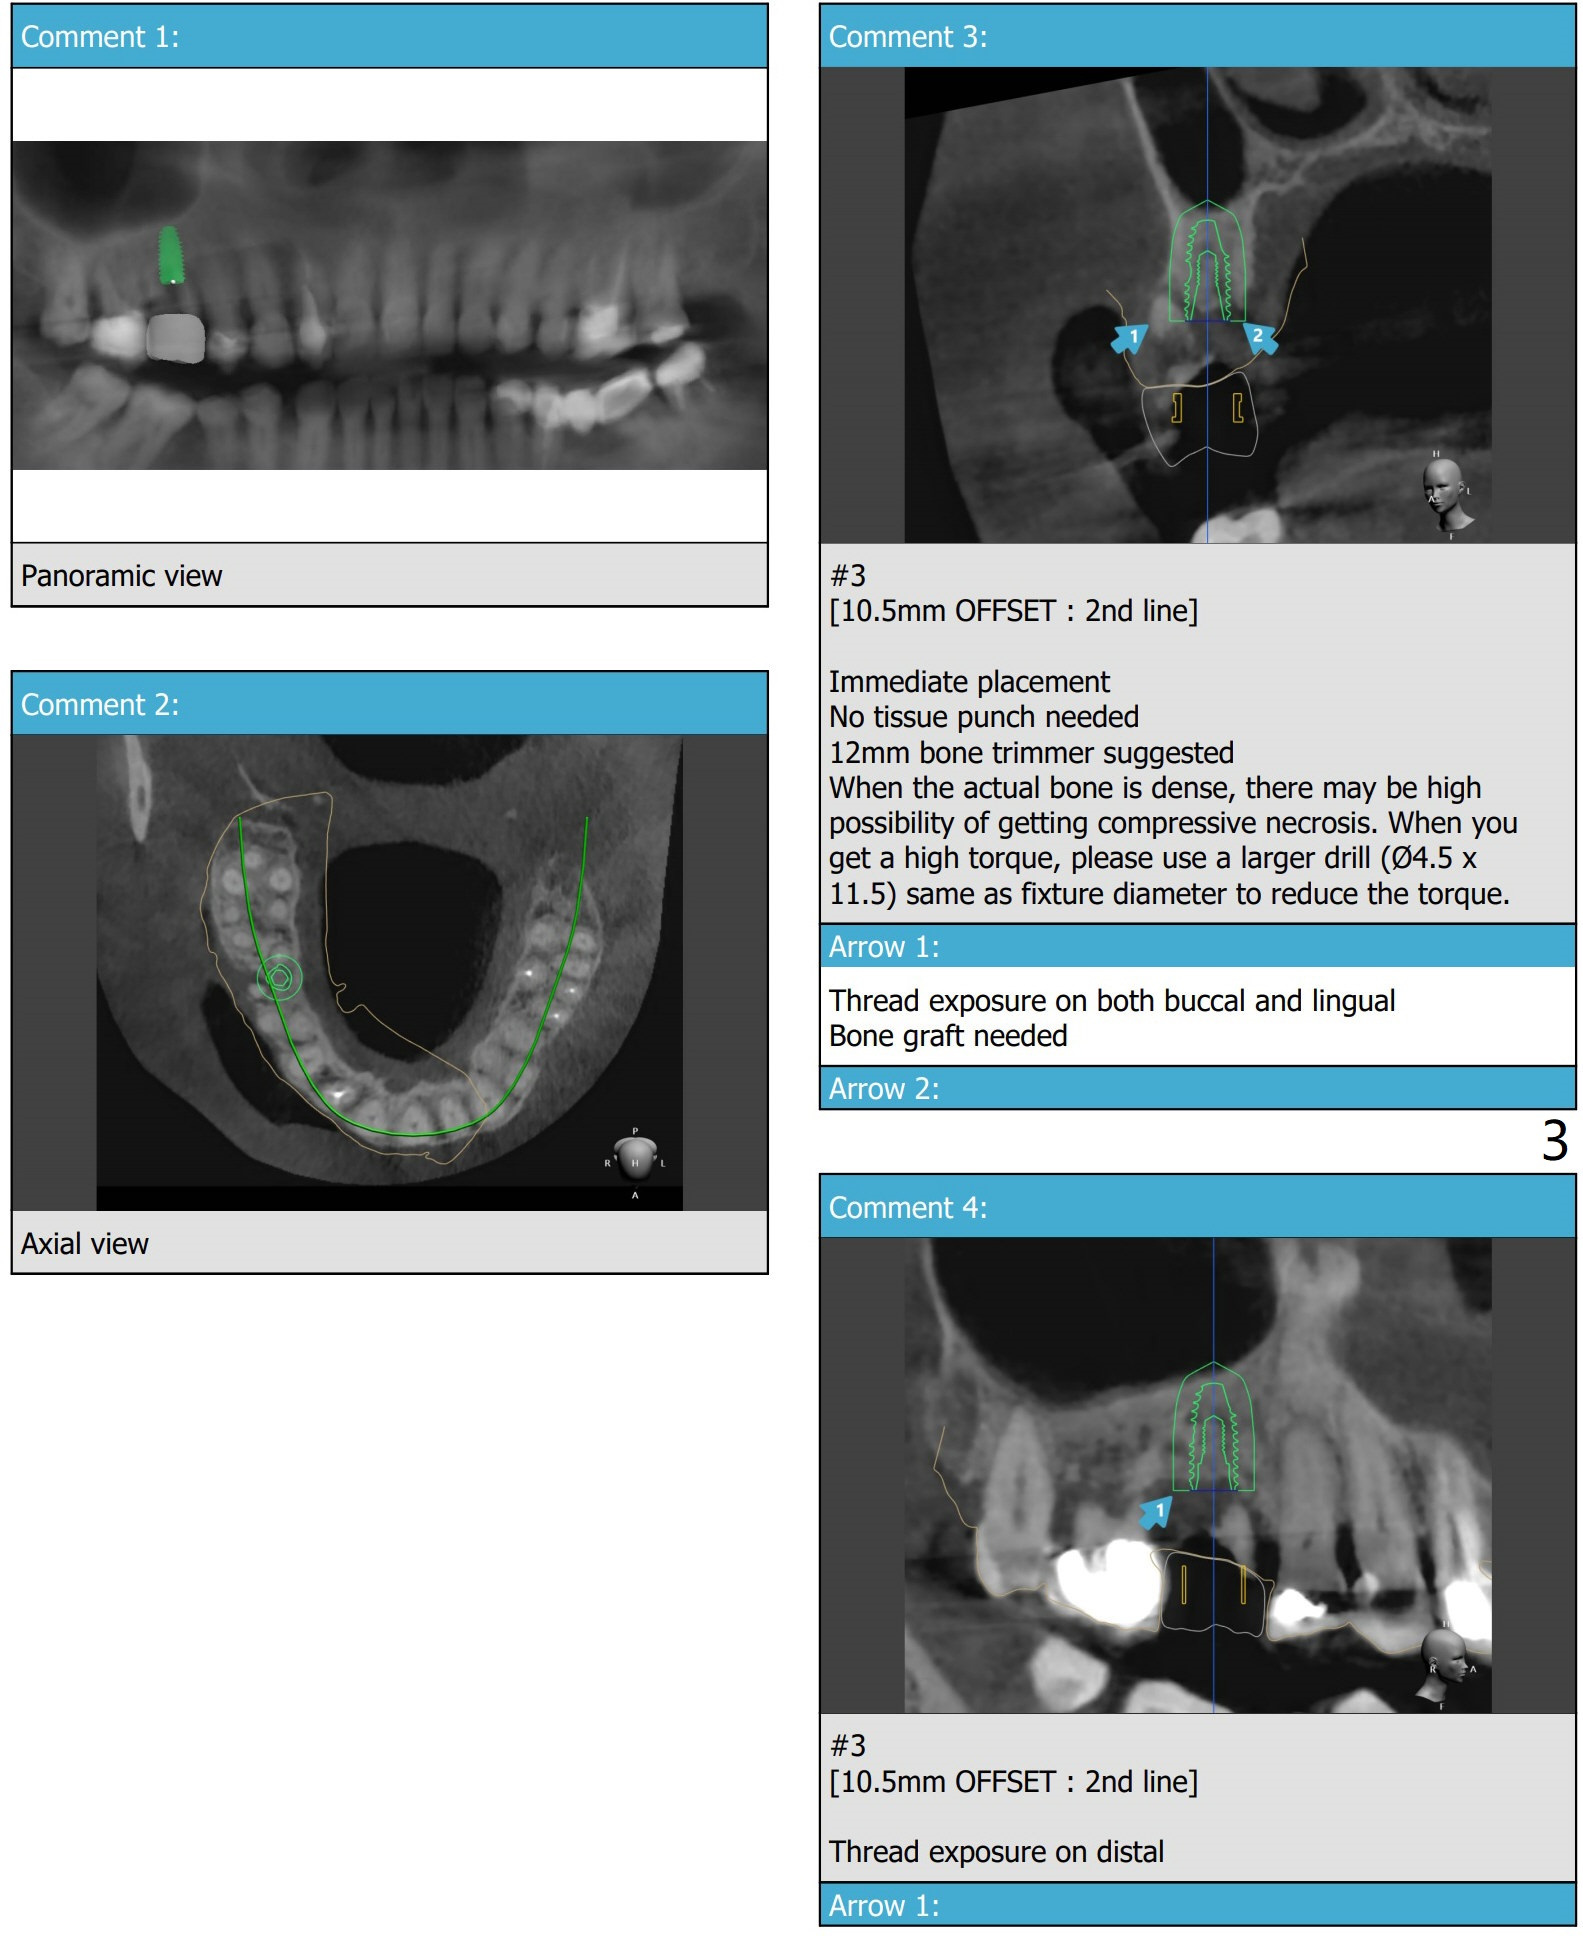

Diagnostic Treatment

A 53-year-old man with light lower lip paresthesia (unknown origin) finally agrees to treat #3 residual roots.